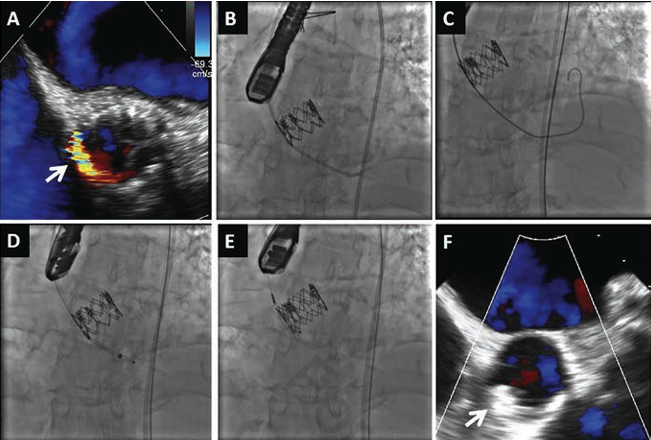

In 1 post-TAVR case, the patient received a transcatheter valve in a 23 mm Hancock II surgical prosthetic valve (Medtronic). The percutaneous PVL closure for this patient was successfully performed in the space between the surgical valve and TAVR valve (Figure 2). Another patient underwent TV-in-TV at 149 days after the index TAVR procedure because of worsening PVL; however, the PVL remained significant and the patient remained symptomatic. Percutaneous PVL closure was attempted 369 days after the index TAVR, but it was unsuccessful due to difficulty advancing the delivery sheath (Figure 3).

Procedure. All PVL closure procedures were approached in a retrograde manner via the femoral artery and performed as previously described.12 The defect site was crossed with an angled or straight hydrophilic guidewire, supported by an appropriate catheter that directed the wire toward the defect. Once the defect was crossed, the support catheter was advanced across the defect and an Amplatz Extra-Stiff wire (Cook Medical, Inc) was advanced into the left ventricle. Once the stiff wire was in place, an appropriately sized delivery sheath was introduced into the left ventricle to deliver the occluder device. The distal end of the device was deployed below the aortic valve. The device was then pulled back into the defect (Figure 1). All occluder devices deployed in this study were Amplatzer Vascular Plug II (AGA Medical), except one Amplatzer PDA and one Amplatzer muscular VSD used in the SAVR group. Single-antiplatelet therapy with aspirin was administrated to all patients after the procedure, and clopidogrel (1 patient) or warfarin (1 patient) was also prescribed based on the comorbidities.

Contrast volume and number of deployed devices during the procedure were significantly greater in the post-SAVR group (30.0 ± 75.0 mL vs 145.0 ± 118.8 mL [P=.01] and 1.0 ± 1.0 vs 1.5 ± 2.0 [P=.01], respectively). This was probably because the PVL closure procedure was more likely to be completed in the SAVR group vs the TAVR group (procedural success rate, 100% vs 60%; P=.04) (Table 2). All successful cases of both groups had immediate PVL improvement during the procedure. On the other hand, all 4 unsuccessful cases in the post-TAVR group had problems with an inability to advance the delivery sheath over the wire and were aborted after multiple attempts (Table 3). Consequently, the post-TAVR group had more PVL ≥moderate after closure (40% vs 0%; P=.04). However, in all 6 procedure-completed cases in this group, postclosure PVL was less than mild and New York Heart Association classes were improved by >1 grade except in 1 patient who expired.